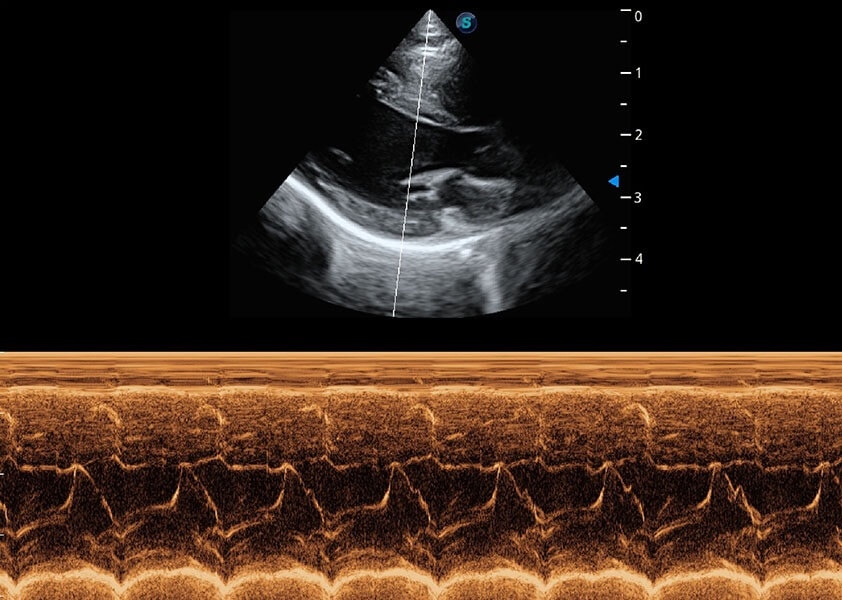

ProPet 60 作為一款高端臺(tái)式動(dòng)物超聲設(shè)備,為動(dòng)物醫(yī)生的日常診斷提供了一系列貼合動(dòng)物臨床需求、解決臨床實(shí)際問(wèn)題的高級(jí)成像功能。憑借全系列高清探頭,滿(mǎn)足醫(yī)生對(duì)腹部、心臟、生殖、淺表、肌骨等成像的所有需求,切實(shí)幫助您提升檢查效率,提高診斷信心。